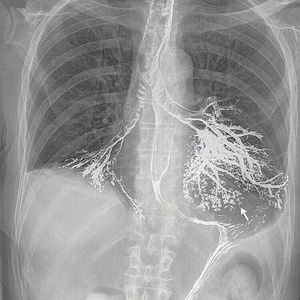

A 79-year-old man was evaluated for unintentional weight loss and dysphagia. He underwent a modified barium swallow. During the rapid-drinking phase, the patient aspirated a large amount of barium (which did not elicit a cough reflex), which resulted in hypoxemic respiratory failure and subsequent intubation. He was admitted to the intensive care unit, and a chest film was obtained. The film showed barium in both the right and left main stem bronchi, outlining the bronchus intermedius, all four lower-lobe basal bronchi, and the segmental bronchi in the left upper and lower lobes. The barium also spread into the smaller airways, producing a tree-in-bud appearance (arrow). The patient underwent bronchoscopy, which confirmed the presence of barium in the right and left lower lobes and lingula. The barium was suctioned extensively. Circulatory shock developed, and the patient had severe anoxic brain injury after cardiac arrest. Despite fluid resuscitation and treatment with inotropic agents and antibiotics, his clinical condition deteriorated, and his family opted for conservative care. He died shortly thereafter.